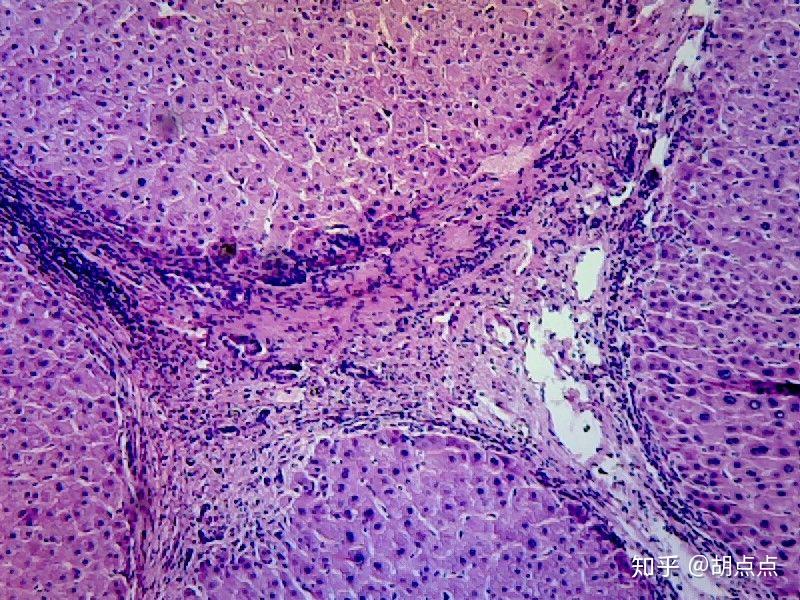

C型肝炎はHCVによって引き起こされる伝染病で、HCVを含む血液や体液との接触によって広がります。この病気は肝臓にダメージを与えます。 C 型肝炎感染症には、急性と慢性の2 つのタイプがあります。

急性C型肝炎は、治療を行わなくても改善または消失する可能性があります。症例の 75 ~ 85% で慢性感染症を引き起こします。慢性型は、肝損傷や肝がんなど、肝臓に長期的な問題を引き起こす可能性があります。

急性C型肝炎は、HCVを含む血液や体液との接触によって広がる伝染性ウイルス感染症です。急性型の病気の主なリスクは、肝障害や肝臓がんを引き起こす可能性がある、より重篤な形態の慢性C型肝炎に進行することです。